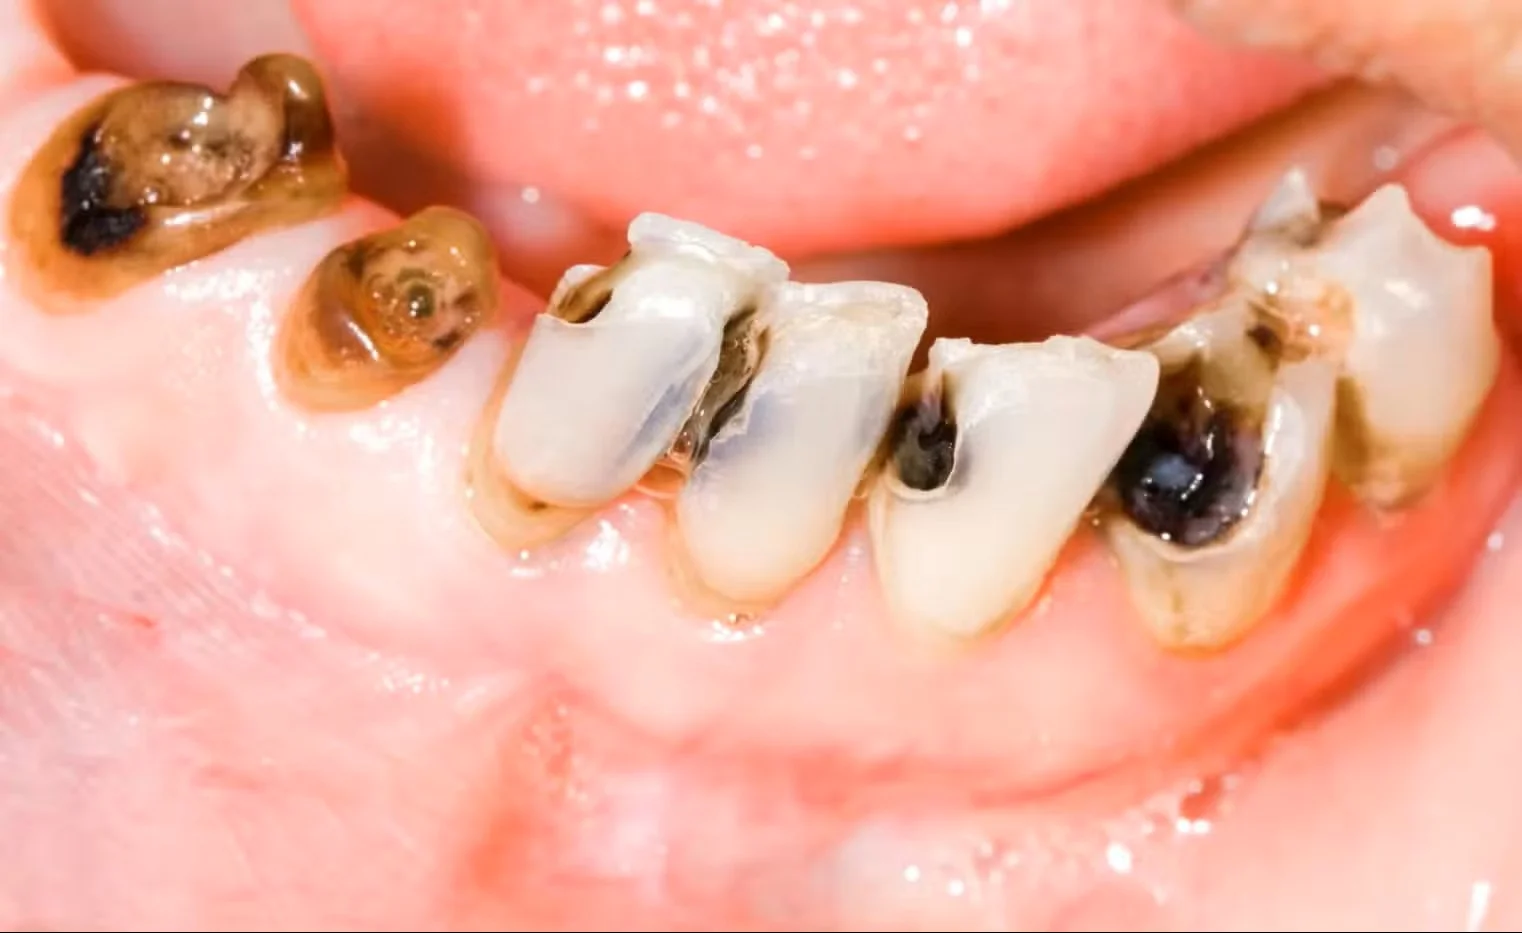

When and Why You May Need a Dental Implant

Extensive decay damaging crown of tooth

Extensive Decay

When a cavity has weakened most of the tooth structure, rebuilding it may no longer be predictable. If the remaining foundation cannot support a long-term restoration, replacing the tooth may be the healthier option.